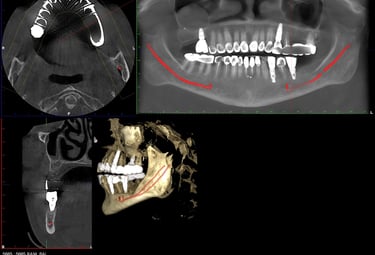

Dental Implants

A long-term solution for missing teeth. Dental implants restore function, appearance, and confidence with a natural-looking, stable result.